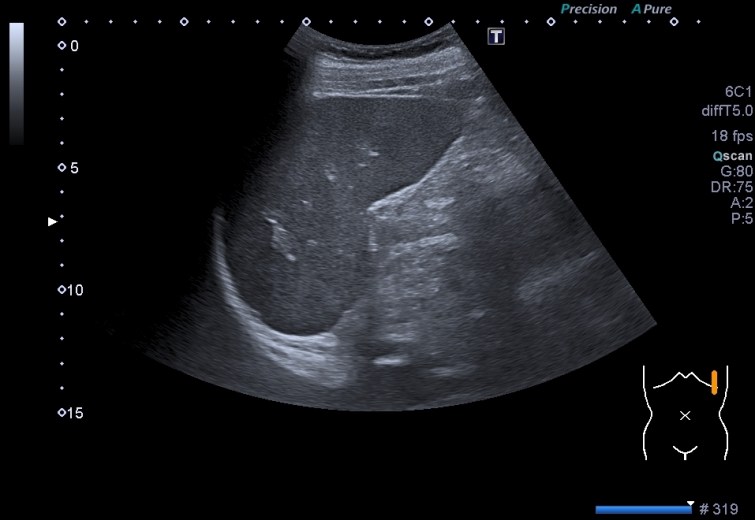

Estas dos imágenes superiores son la normalidad. Corte axial y longitudinal del Bazo. Homogéneo, sin lesiones, grande sin llegar a la esplenomegalia. Bazo de libro.

Toca ahora ver las imágenes patológicas:

Observas, semiólogicamente hablando, un bazo con una gran cantidad de lesiones ocupantes de espacio, hiperecogénicas que afectan a toda la ecoestructura. Doppler normal.